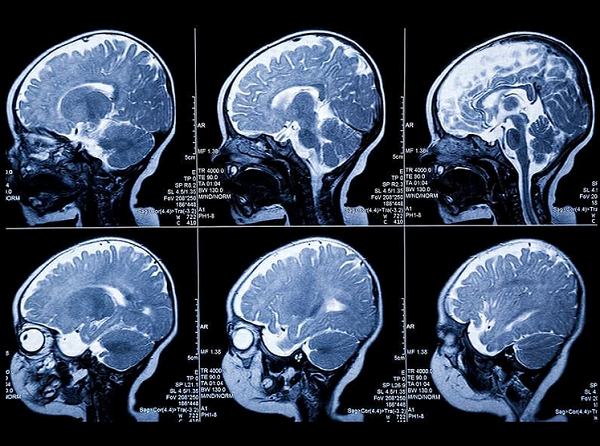

МРТ головного мозга. В указанную стоимость входит проведение сканирования, описание результатов исследования на фирменном бланке, выдача результатов МРТ в полном объёме на компакт диске (CD) или в виде жёсткой копии на плёнке. При желании вы можете заказать большее количество носителей.

МРТ с эпилептическим протоколом – это высокоточное исследование, направленное на диагностику патологий головного мозга, связанных с эпилепсией. Процедура позволяет выявить структурные изменения, которые могут быть причиной судорожной активности.